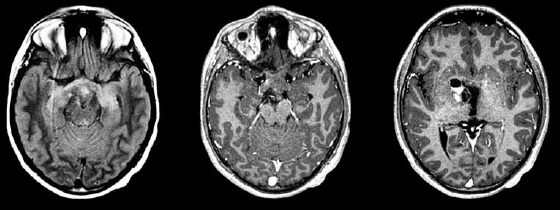

Paciente de 2 anos apresenta nistagmo e perda visual há 3 meses. Realizou o exame de imagem a seguir.

Qual é o provável diagnóstico?